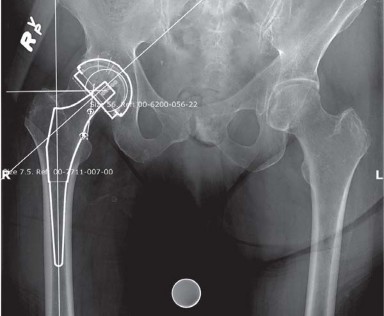

Introduction Short stem femoral implants are rapidly gaining importance because an increasing numbers of youn…